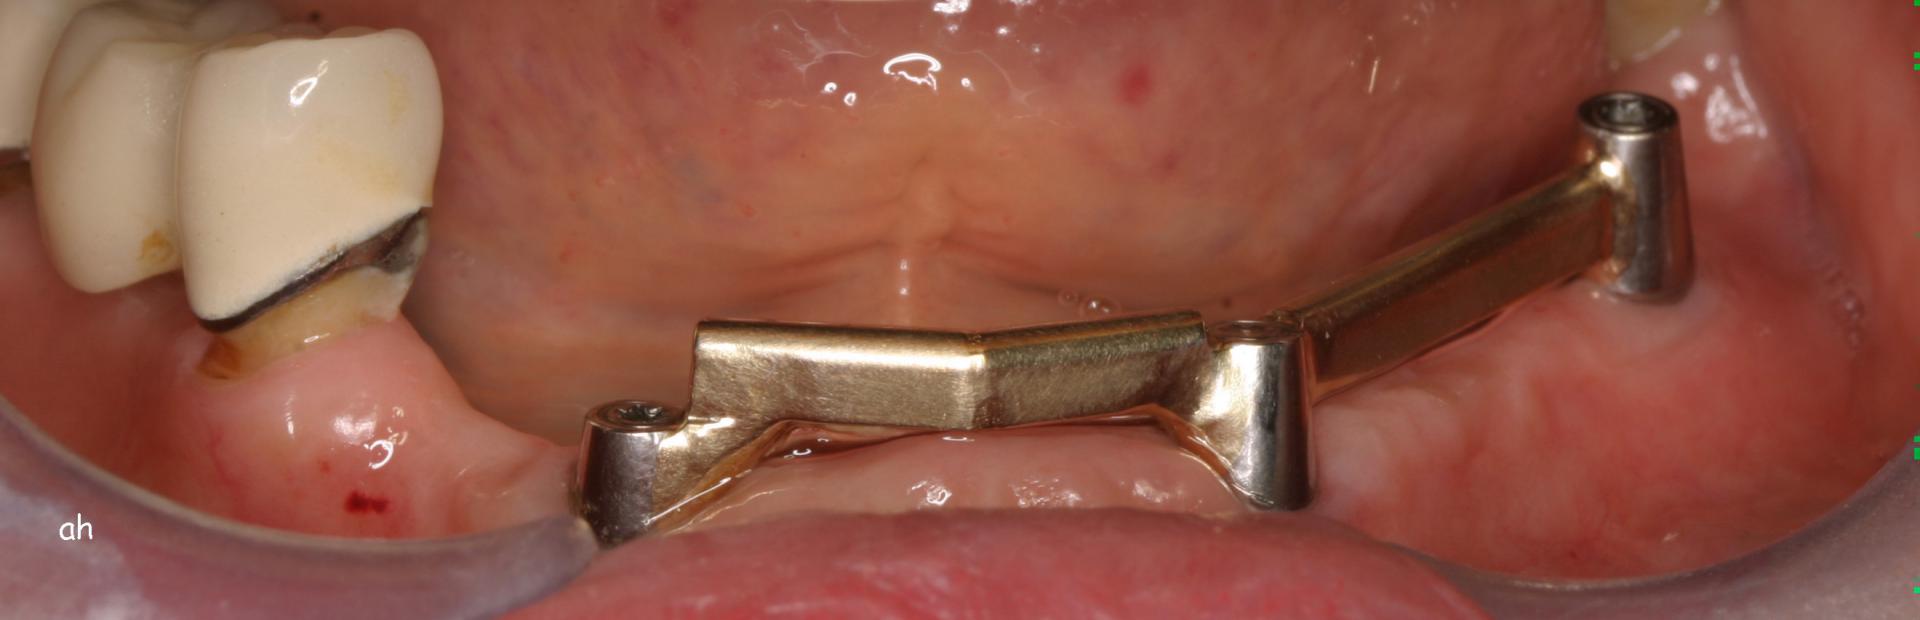

Exemple 9: Un cas complexe, 3 implants on été mis au niveau de la mandibule.

Exemple 9: Une barre est vissée sur ces 3 implants.

Exemple 9: Puis un appareil amovible est fixé sur cette barre.